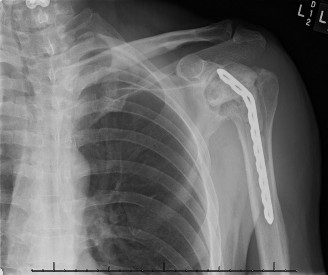

CASE 20 A 72-year-old, right-hand-dominant male with a history of type 2 diabetes, hypertension, and coronary artery disease presents to clinic for a second opinion regarding worsening left shoulder pain 8 months after undergoing a left total shoulder arthroplasty. He had an uncomplicated procedure and has had no major postoperative complications thus far; however, he has never been completely pain free since his procedure. He denies any recent trauma, fevers, chills, or drainage from the incision site. On examination, the incision sites are clean, dry, and intact, and he has mild tenderness to palpation diffusely over the left shoulder as well as decreased range of motion. Imaging is shown in Figure 2–55.

Figure 2–55

CT arthrograms of the patient’s left shoulder are shown in Figure 2–56. CRP is <3, ESR 45. The patient continues to have pain, so you decide to perform arthroscopic biopsy to obtain tissue cultures. Frozen sections show <5 PMNs per hpf, and Gram stains are all negative.

Figure 2–56

The correct answer is (B). Figure shows contrast under the glenoid component. Given the patient’s normal inflammatory markers and frozen sections combined with continued pain and loosening on CT, infection with P. acnes(an organism that is very difficult to isolate) should be investigated by holding any cultures for at least 2 weeks to see if it will eventually grow. Chocolate agar (Choice C) is mainly used for growing species such as H. influenzae and Neisseria meningitidis not P. acnes. A is incorrect since the patient’s cell count and frozen sections are clearly abnormal, therefore referral to pain clinic would not be appropriate. However, Choice D would be too aggressive an approach given that no organisms have been isolated, frozen sections show <5 PMNs per hpf, and the patient has relatively normal inflammatory markers.

The patient undergoes resection arthroplasty with antibiotic cement spacer and a 6-week course of IV antibiotics. He returns to clinic 4 months later with improved pain, CRP <3, however, on examination he has a positive belly press sign and increased external rotation compared with the contralateral shoulder. Imaging is shown in Figure 2–57.

Figure 2–57

The correct answer is (D). The patient has completed his course of antibiotics and his spacer and is now an appropriate candidate for explanation of the cement spacer with revision shoulder arthroplasty, therefore Choices A and C are incorrect. The patient’s clinical examination findings point to rotator cuff tear (specifically subscapularis) which has occurred in the interval between his obtaining his initial total shoulder arthroplasty and his current examination. Therefore, total shoulder arthroplasty (Choice B) is contraindicated, and the patient should have a reverse total shoulder arthroplasty. Objectives: Did you learn...? Recognize the clinical presentation of a patient with infection after total shoulder arthroplasty?